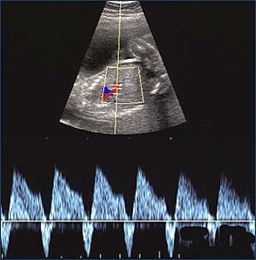

On the recipient side, there is gradual improvement in heart failure from the abnormal tracing before the laser treatment (part of the blood flow in the heart cycle runs backwards, on the left) to normal cardiac function with all blood flow forward (on the right).